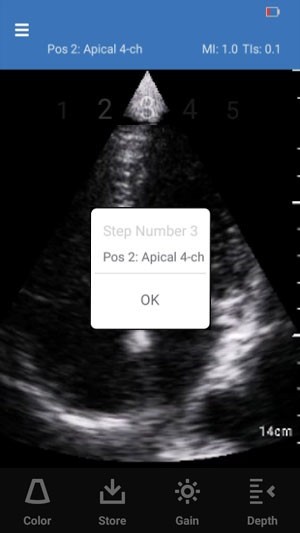

3. User Instructions message box displays for the step.

4. Press OK on the message box to navigate to the scan screen.

User instructions